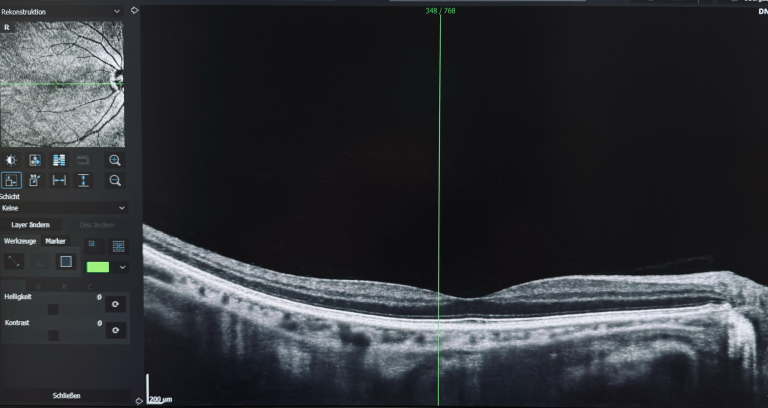

Optische Kohärenztomographie

Die optische Kohärenztomographie (OCT) ist ein modernes bildgebendes Verfahren, das in der Augenheilkunde an Bedeutung gewinnt. Es bietet die Möglichkeit, die Schichten der Netzhaut mit hoher Auflösung darzustellen und wird häufig zur Diagnose sowie zur Überwachung von Augenkrankheiten eingesetzt, darunter diabetische Retinopathie, Glaukom und altersbedingte Makuladegeneration. Dank der nicht-invasiven Eigenschaften der OCT können Augenärzte präzise Informationen über die Anatomie und den Gesundheitszustand der Netzhaut gewinnen. Dies ermöglicht frühzeitige Behandlungsansätze und die Anpassung individueller Therapiestrategien.